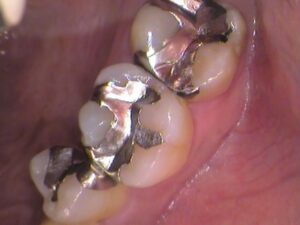

お口の中を見てみると

上の奥歯ですが、銀歯が入っています。

何年も前に虫歯治療をしたときに銀歯になったそうです。

この銀歯の中で虫歯が広がっています。